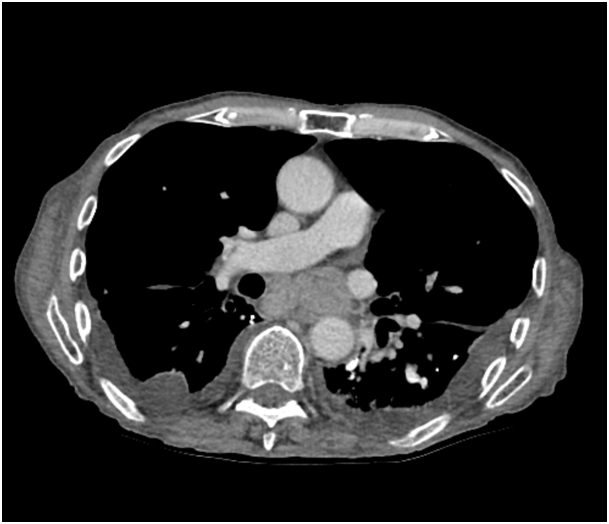

A 77 year old male nursing home resident presented a four week history of dyspnoea, non-productive cough, progressive dysphagia and generalised fatigue. He denied any appetite change or weight loss, fevers or night sweats, chest pain, haemoptysis or wheeze. He was a lifelong non-smoker, exposed to asbestos whilst working in a shoe factory. Clinical examination revealed decreased breath sounds and crackles in the left lower zone, but no peripheral lymphadenopathy or hepatosplenomegaly. Computerised tomography of the chest, abdomen and pelvis was carried out (Figure 1). Bilateral pleural effusions were seen, with left lower lobe consolidation. Meditational and right hilar lymphadenopathy compressing the oesophagus was noted and pleural calcifications suggested previous asbestos exposure.

Figure 1 Computerised tomography of the chest showing bilateral pleural effusions and meditational lymphadenopathy.